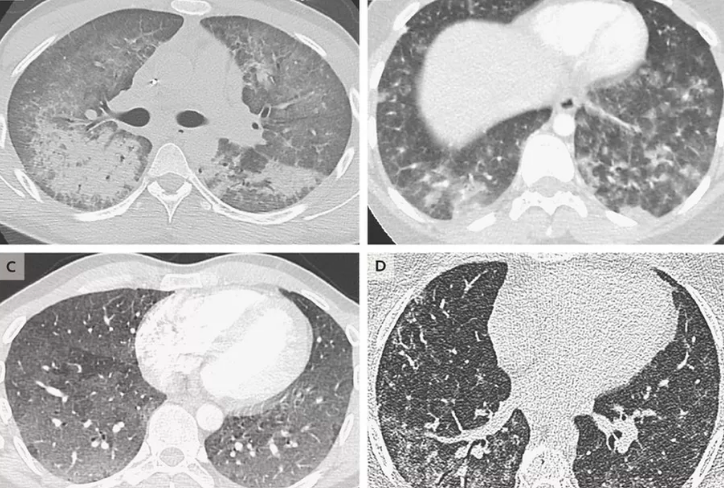

The doctor treating the woman confirmed that though she had some previous medical illness, nothing was serious until she started using e-cigarettes for the first time. She died due to full-blown acute respiratory distress syndrome.

Symptoms of illness related to aping majorly include shortness of breath, fever, coughing and vomiting. Additionally, headaches, dizziness and chest pain are some of the extreme symptoms.